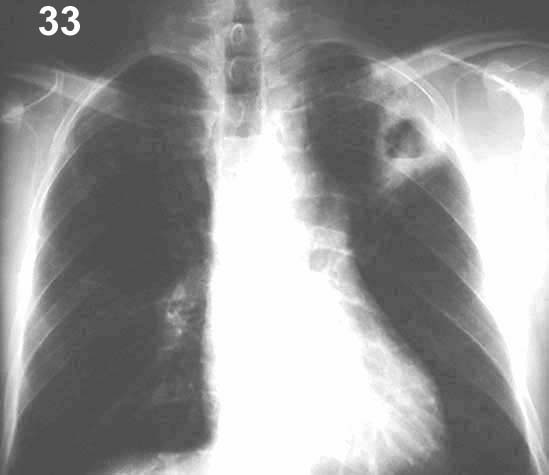

Placa 33